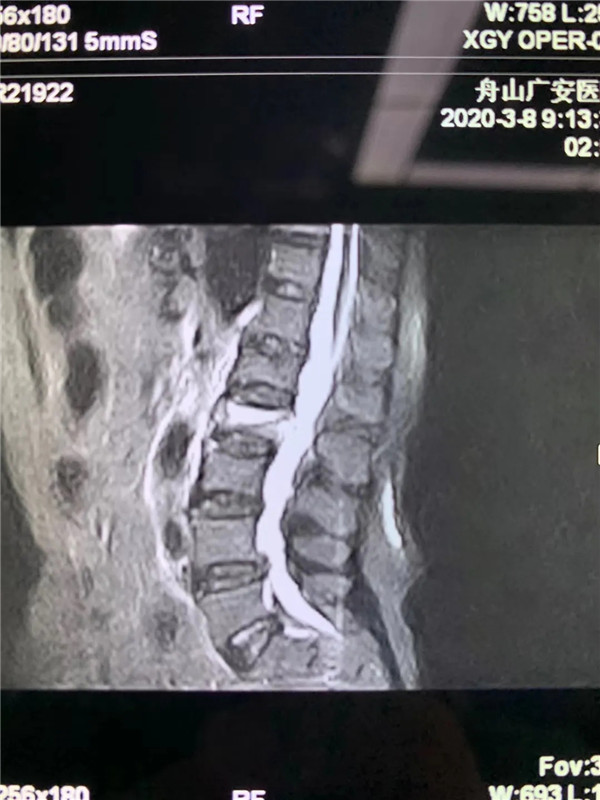

經(jīng)過(guò)仔細(xì)問(wèn)診和查體后,初步診斷曹阿姨是椎體壓縮骨折了,在完善胸腰椎的MRI線檢查后,也證實(shí)了推斷。在與曹阿姨及家屬充分溝通后,戈才華主任為曹阿姨實(shí)施了微創(chuàng)手術(shù),很快為其緩解了疼痛。

(MRI顯示椎體壓縮性骨折)